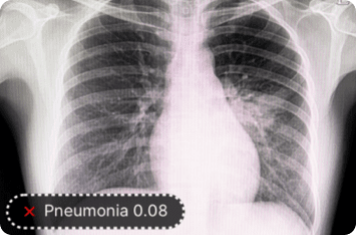

Enhance the accuracy of MRI, CT, PET, X-ray, and ultrasound image analysis by training models in LandingLens to detect abnormalities. LandingLens can review thousands of images looking for anomalies or diagnostic mismatches that deserve further investigation.

In addition to detecting whether or not a disease or condition is present, models from LandingLens can also determine how advanced a condition is. For example, LandingLens can be trained to classify stages of knee osteoarthritis (OA).